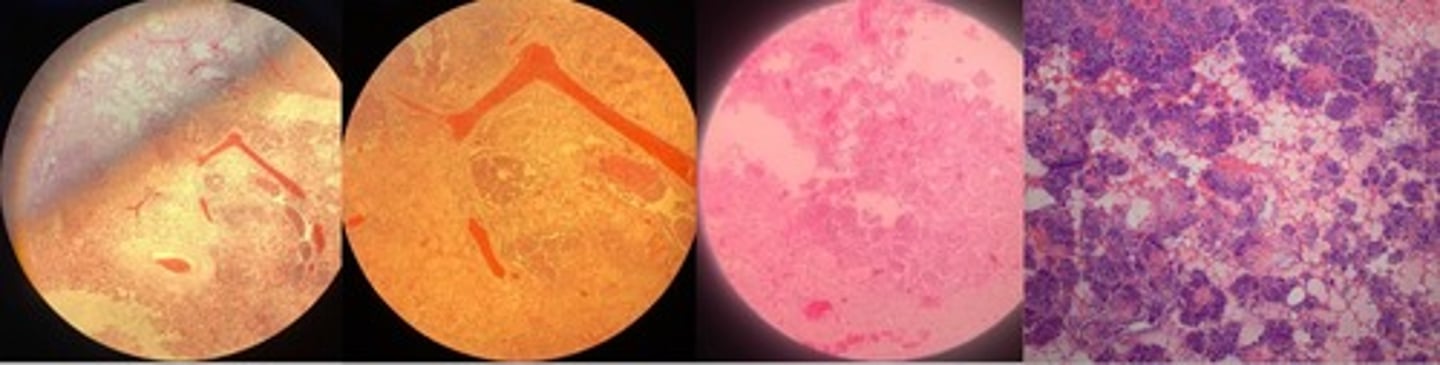

Bacterial embolic purulent nephritis

- bacterial emboli formed in capillary vessels and bv’s

- degen of tubular epi cells

- at edge of bacteria emboli => microabscess (neutrophils w/ debris)